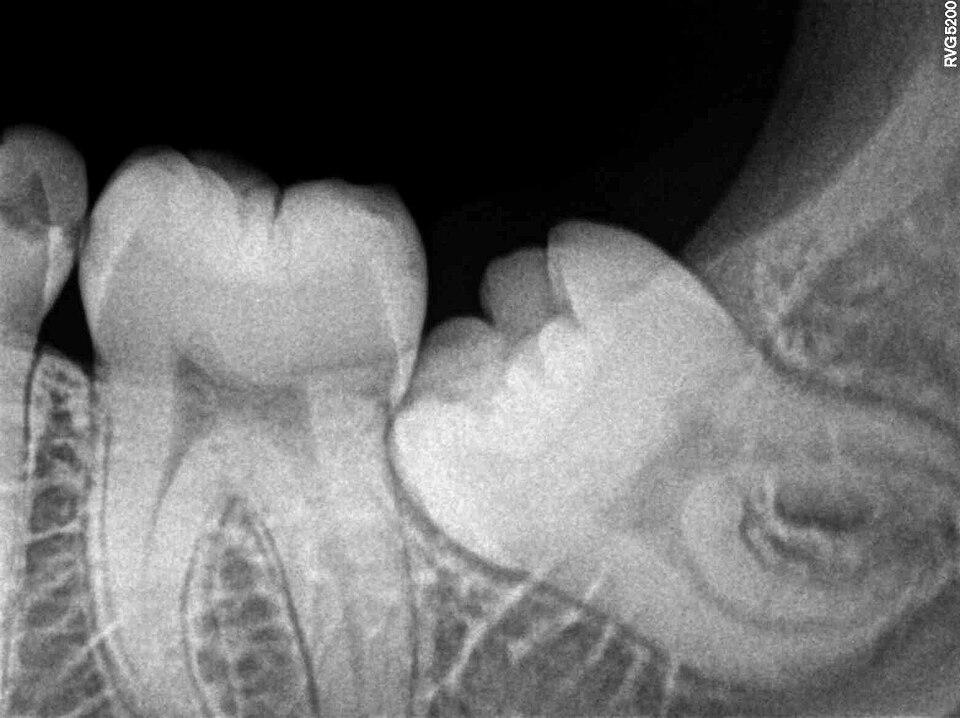

The third molars, commonly known as wisdom teeth, are the last teeth to erupt in the human mouth, typically appearing between the ages of 17 and 25.

Dental X-ray showing an impacted lower left third molar (wisdom tooth) tilted against the adjacent second molar

Dental radiograph of an impacted lower left third molar (wisdom tooth), wedged at an angle against the second molar. Impaction rates of 30 to 70 percent in modern humans reflect the mismatch between inherited tooth size and a jaw that has shrunk over millions of years of dietary change. Nizil Shah, Wikimedia Commons, CC BY-SA 4.0

In a substantial proportion of modern humans, they fail to erupt properly or become impacted—trapped beneath the gum line or wedged against adjacent teeth—because the modern human jaw is simply too small to accommodate them.9, 10 This mismatch between tooth size and jaw size is a hallmark of vestigiality: the teeth are inherited from ancestors with larger jaws, but the jaws have since shrunk while the genetic instructions for producing third molars remain largely intact.10

The clinical consequences are dramatic. Studies of third molar impaction in modern populations find rates ranging from 30% to over 70%, depending on the population studied.9 A 2021 review in the Journal of Clinical Medicine found that the retromolar space—the gap behind the second molar where wisdom teeth must erupt—is significantly smaller in modern humans than in earlier hominin species, directly explaining the high impaction rate.9 Furthermore, agenesis of the third molar (congenital absence of one or more wisdom teeth) affects an estimated 20 to 25% of the global population, with higher rates in certain populations, indicating that natural selection may be in the process of eliminating these teeth entirely.10, 13